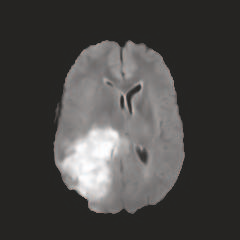

Multi-modal medical image completion has been extensively applied to alleviate the missing modality issue in a wealth of multi-modal diagnostic tasks. However, for most existing synthesis methods, their inferences of missing modalities can collapse into a deterministic mapping from the available ones, ignoring the uncertainties inherent in the cross-modal relationships. Here, we propose the Unified Multi-Modal Conditional Score-based Generative Model (UMM-CSGM) to take advantage of Score-based Generative Model (SGM) in modeling and stochastically sampling a target probability distribution, and further extend SGM to cross-modal conditional synthesis for various missing-modality configurations in a unified framework. Specifically, UMM-CSGM employs a novel multi-in multi-out Conditional Score Network (mm-CSN) to learn a comprehensive set of cross-modal conditional distributions via conditional diffusion and reverse generation in the complete modality space. In this way, the generation process can be accurately conditioned by all available information, and can fit all possible configurations of missing modalities in a single network. Experiments on BraTS19 dataset show that the UMM-CSGM can more reliably synthesize the heterogeneous enhancement and irregular area in tumor-induced lesions for any missing modalities.